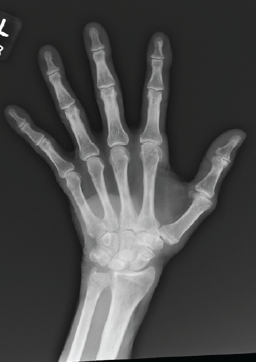

Distal Femur Extension Osteotomy for Fixed Flexion Deformity Following Distal Femur Malunion – A Case Report